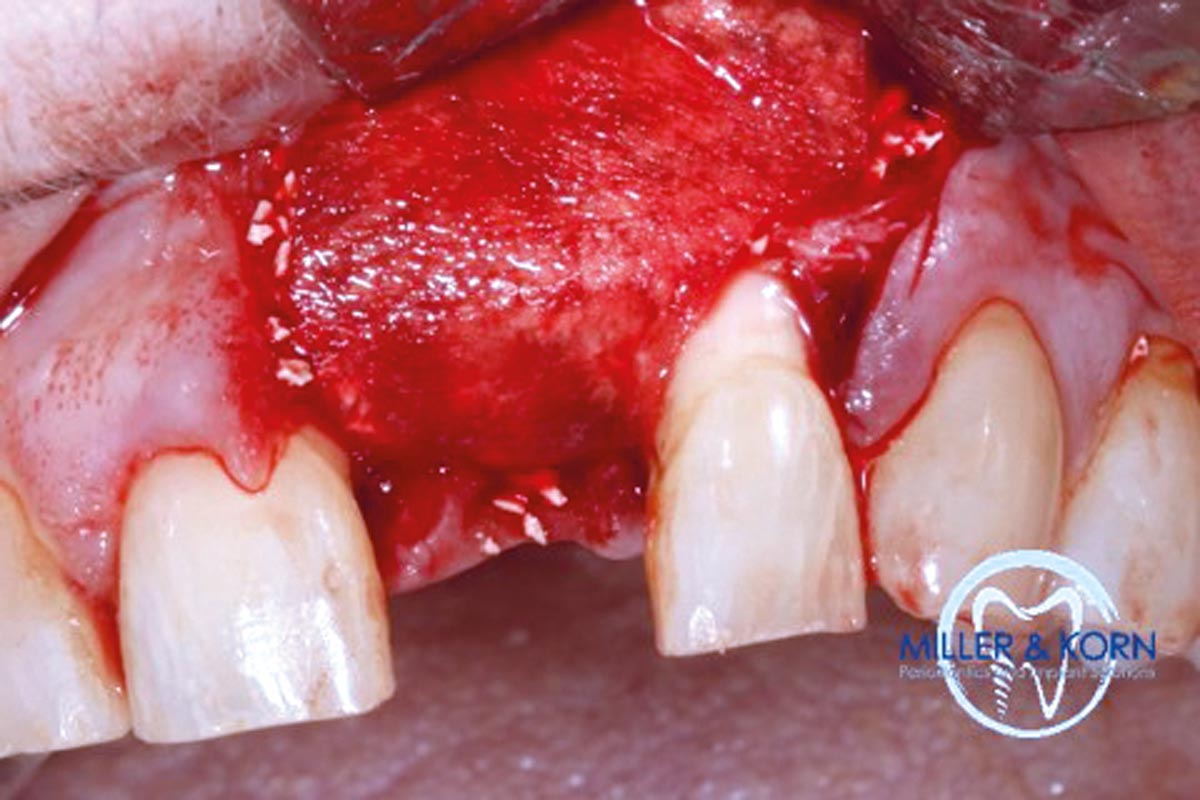

04/39 - Preparation of a full thickness flap and careful debridementImmediate implant placement and correction of horizontal and vertical bone loss using an allograft bone ring, cerabone® and Jason® membrane - Drs. Miller and Korn